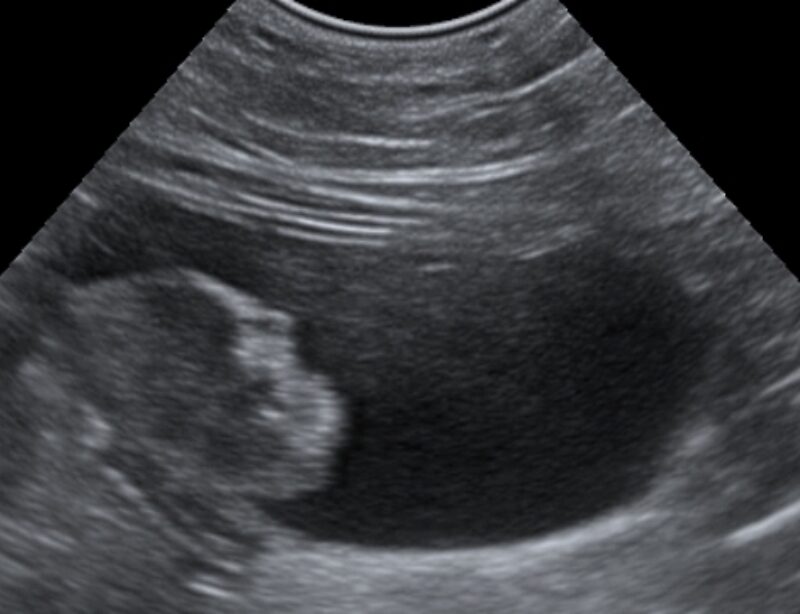

Sowohl eine Blasenentzündung als auch gut- oder bösartige Tumoren der Harnblase können beim Hund zu ähnlichen klinischen Symptomen führen, wie zum Beispiel zu blutigem Urin, Harnabsatzproblemen oder Inkontinenz. Nach der allgemeinen und speziellen klinischen Untersuchung kann die Harnblase mittels Ultraschall genauer angeschaut werden, um mögliche Tumoren zu identizieren. Zur weiteren Diagnostik kann je nach Lage des Falles eine Laboruntersuchung des Urins auf das Vorhandensein von Bakterien, Kristallen oder Tumorzellen notwendig sein.

Die Methode ist daher vor allem sinnvoll, wenn andere Verfahren keine eindeutige Diagnose liefern oder nur Urin für die Untersuchung zur Verfügung steht. Der Vorteil für den Patienten ist, dass zunächst Urin(sediment) untersucht werden kann, ohne dass ein invasives Verfahren wie eine Ansaug- oder Exzisionsbiopsie nötig ist. Eine spätere Ultraschalluntersuchung oder eine Endoskopie ist dann aber sowohl bei einem positiven als auch bei einem negativen molekulargenetischen Ergebnis notwendig, um im positiven Fall den Tumor genauer zu charakterisieren bzw. einen falsch negativen Befund auszuschließen.